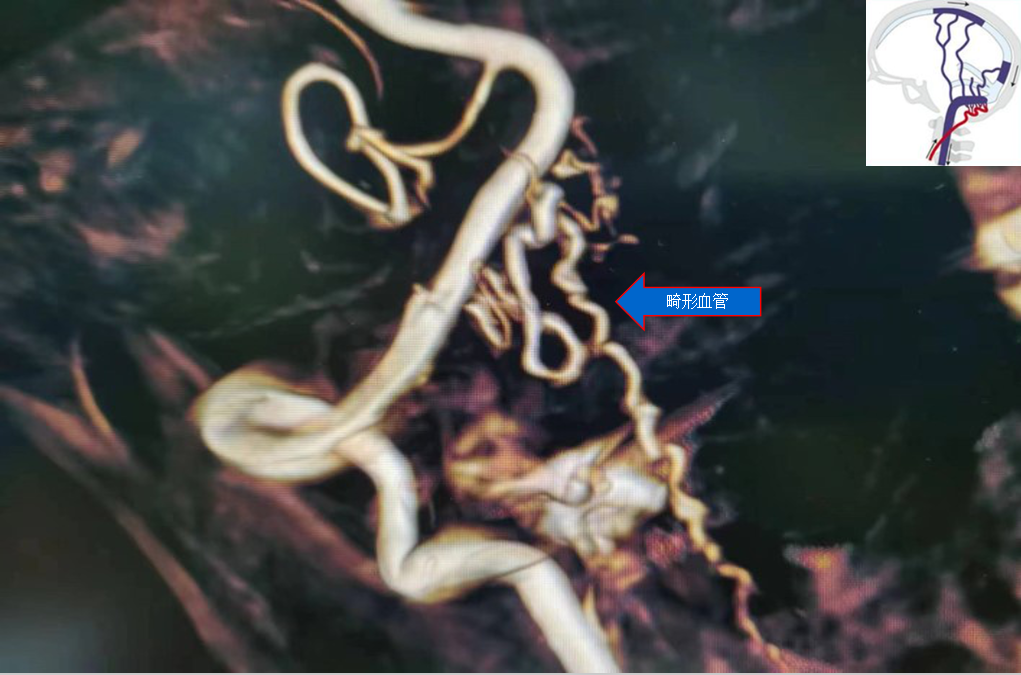

62岁的黄先生因“反复头晕伴呕吐1月余 ”来到柳州市工人医院住院。颅脑MRI及DWI、MRA提示:延髓异常信号灶,考虑动静脉畸形并局部胶质增生,变性可能性大;脑、脊髓血管造影提示:枕颈交界区硬脑膜动静脉瘘,瘘口位于椎动脉硬脊膜入颅处。

术前CTA: 颅颈交界区硬脑膜动静脉瘘

经过神经外科医师团队讨论,根据患者病情,畸形血管瘘口迂曲细小,介入栓塞导管估计难以置入,或者术中发生破裂出血、脑干梗塞的风险极高,综合判断,开颅手术夹闭瘘口才是最适合黄先生的治疗方案。采用术式:复合手术室下行开颅颅颈交界区硬脑膜动静脉瘘夹闭术。步骤:左侧桡动脉穿刺留置5F造影管至左椎动脉、俯卧位、左侧枕部旁正中 。